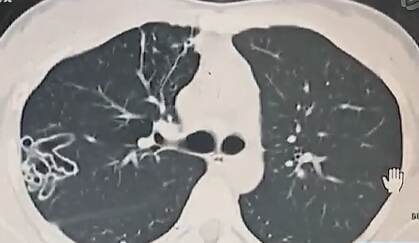

• 女孩吃小龍蝦 肺部現(xiàn)空洞